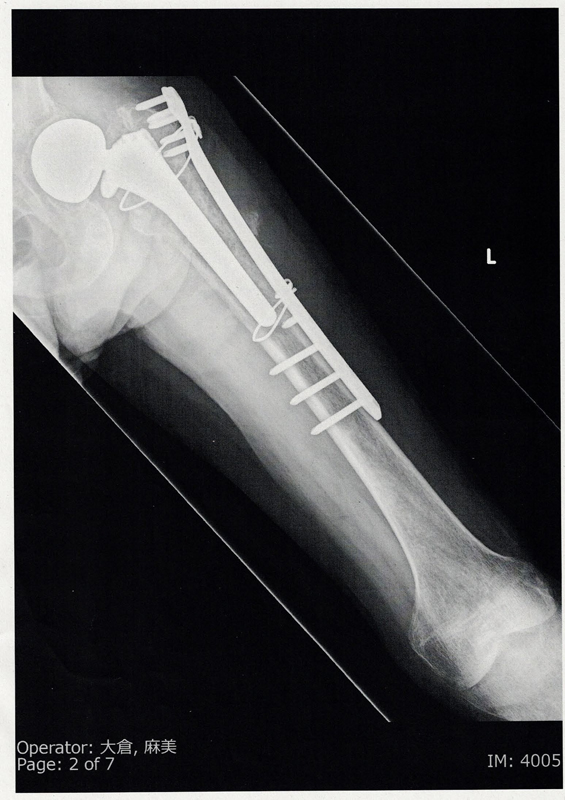

このCTスキャンで骨格が明確に観察され、左脚の大腿骨が斜めに骨折しているのがわかる。

前立腺がんが大腿骨に転移していたのだ。

観血的整復固定術、

後からパスを見たら、「左大腿骨近位端病的骨折」

私の場合、人工骨頭なので若干異なり、チタン合金製の人工骨頭を大腿骨の中にスポット入れたわけで、その大腿骨の上部に前立腺がんが転移し、そこが骨折したわけである。

30cmくらい切られており、病室でも左脚に免荷、即ち一切荷重をかけるなとなっている。